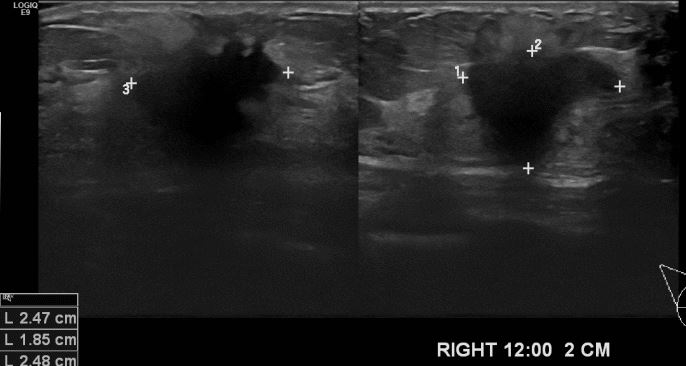

상기 환자 우측 유방에 만져지는 멍우리로 내원하신 40대 여성 분으로 유방 초음파

시행후 우측 12시 방향 2cm 떨어진 거리의 혹 조직검사 시행하여 우측 침윤성 유관암

진단 되었습니다.